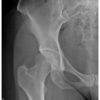

Chú thích: 1. Mào chậu; 2. Hố chỏm đùi; 3. Gai chậu trước dưới; 4. Thân xương mu; 5. Ngành dưới xương mu; 6. Khớp cùng chậu; 7. Lỗ bịt; 8. Ụ ngồi; 9. Ngành xương ngồi; 11. Gai ngồi; 12. Ổ cối; 13. Vành trước ổ cối; 14. Đường chậu ngồi; 15. Cổ xương đùi; 16. Mấu chuyển nhỏ; 17. Đường gian mấu; 18. Cánh xương cùng; 19. Gai chậu trước trên; 20. Đường cung; 21. Thân xương đùi; 22. Mào xương cùng; 23. Xương cụt; 24-25-28. Khớp háng; 26. Gai chậu sau trên; 27. Chỏm xương đùi; 29. Khớp mu; 30. Mỡ bao khớp; 31. Ngành trên xương mu; 32. Mỡ cơ mông; 33. Mấu chuyển lớn; 34. Đường mỡ cơ thắt lưng chậu; 35. Hơi trong ruột non; 36. Bàng quang; 37. Cơ mông; 38. Vôi hóa mạch máu; 39. Gai sau L4; 40. Xương cánh chậu; 41. Gai sau L5; 42. Koehler’s teardrop; 43. Vành sau ổ cối; 44. Lỗ cùng. Chú thích: 1. Mào chậu; 2. Hố chỏm đùi; 3. Gai chậu trước dưới; 4. Thân xương mu; 5. Ngành dưới xương mu; 6. Khớp cùng chậu; 7. Lỗ bịt; 8. Ụ ngồi; 9. Ngành xương ngồi; 11. Gai ngồi; 12. Ổ cối; 13. Vành trước ổ cối; 14. Đường chậu ngồi; 15. Cổ xương đùi; 16. Mấu chuyển nhỏ; 17. Đường gian mấu; 18. Cánh xương cùng; 19. Gai chậu trước trên; 20. Đường cung; 21. Thân xương đùi; 22. Mào xương cùng; 23. Xương cụt; 24-25-28. Khớp háng; 26. Gai chậu sau trên; 27. Chỏm xương đùi; 29. Khớp mu; 30. Mỡ bao khớp; 31. Ngành trên xương mu; 32. Mỡ cơ mông; 33. Mấu chuyển lớn; 34. Đường mỡ cơ thắt lưng chậu; 35. Hơi trong ruột non; 36. Bàng quang; 37. Cơ mông; 38. Vôi hóa mạch máu; 39. Gai sau L4; 40. Xương cánh chậu; 41. Gai sau L5; 42. Koehler’s teardrop; 43. Vành sau ổ cối; 44. Lỗ cùng. – Gãy chỏm xương đùi còn được gọi là gãy trật khớp chỏm xương đùi, là những chấn thương hiếm gặp, đại diện cho loại gãy xương đầu gần xương đùi ít phổ biến nhất và hầu hết các trường hợp liên quan đến trật khớp háng. Có tới 15% tất cả các trường hợp trật khớp háng ra sau liên quan đến gãy chỏm xương đùi. – Loại I: gãy xương kéo dài xuống dưới/đuôi của hõm chỏm xương đùi – Mảnh vỡ chỏm xương đùi bị di lệch. => Case lâm sàng 1: – Gãy cổ xương đùi (NOF) là những chấn thương phổ biến ở bệnh nhân lớn tuổi, những người có khả năng bị mất thăng bằng khi đi lại và giảm mật độ xương, dẫn đến nguy cơ gãy xương. Phụ nữ cao tuổi bị loãng xương có nguy cơ cao nhất. – Nguyên nhân: * Đường gãy (Linton): Dựa vào vị trí đường gãy cổ xương đùi * Độ chếch đường gãy: * Loại gãy (Garden – dựa vào sự di lệch của ổ gãy) => Case lâm sàng: * Nguy cơ hoại tử vô mạch – Phần lớn nguồn cung cấp máu cho chỏm xương đùi được thực hiện bởi vòng động mạch ngoài bao, được hình thành bởi động mạch mũ đùi ngoài và động mạch mũ đùi trong. – Gián đoạn đường Shenton: – Bình thường các bè xương vùng cổ xương đùi đều và liên tục. Nếu mất liên tục và gập góc các bè xương => nghi ngờ gãy xương. – Mấu chuyển bé bên xương gãy rõ hơn bên đối diện do xương đùi bên gãy xoay ngoài. – Đường sáng mất liên tục vỏ xương. – Cổ xương đùi ngắn, mất cân đối chỏm – cổ xương đùi so với bên đối diện. – Gãy mấu chuyển là gãy xương liên quan đến mấu chuyển lớn và/hoặc mấu chuyển bé của xương đùi. – Gãy liên mấu chuyển: – Trật khớp háng là sự di lệch hoàn toàn hay không hoàn toàn mặt khớp của chỏm xương đùi và ổ cối. Nguyên nhân do bẩm sinh hoặc mắc phải. Khớp háng là khớp lớn và vững chắc nhất trong các khớp. Nếu khớp háng trật được thì lực chấn thương tác động rất mạnh. Do đó, cần chú ý các tổn thương đi kèm gãy xương, tổn thương thần kinh, mạch máu, thậm chí chấn thương các cơ quan khác. * Nguyên nhân * Vị trí chỏm xương đùi – ổ cối * Phân loại theo Thompson- Epstein * Phân loại theo Pipkin * Hình thái tổn thương: * Trật khớp háng ra sau * Trật khớp háng ra trước * Trật khớp trung tâm – Loạn sản khớp háng tiến triển (Developmental dysplasia of the hip – DDH) trước đây được ghi nhận như trật khớp háng bẩm sinh (Congenital Dislocation of the Hip = CDH) là sự bất thường cấu tạo khớp háng, trong đó chỏm xương đùi không được giữ vững trong ổ khớp. * Nguyên nhân * Đặc điểm hình ảnh – Độ bao phủ ổ cối: – Đường Hilgenreiner: đường nằm ngang và đi qua khe sáng của đáy ổ cối (điểm cao nhất của khe sáng) – trung tâm của các sụn tam hợp – vị trí nơi 3 xương chậu (xương mu, xương ngồi, xương cánh chậu) gặp nhau. Bình thường chỏm xương đùi nằm dưới đường này. – Đường Ombredanne (Perkins): đứng dọc, vuông góc với đường Hilgenreiner và đi qua điểm ngoài cùng của ổ cối. Bình thường chỏm nằm phía trong đường này. – Đường Hilgenreiner & Đường Ombredanne: bình thường điểm cốt hóa chỏm xương đùi nằm ở góc 1/4 dưới trong của hệ trục 2 chiều tạo bởi đường Hilgenreiner và đường Ombredanne. – Góc ổ cối (Acetabular angle): – Gián đoạn đường Shenton: => Case lâm sàng 1: => Case lâm sàng 2: => Case lâm sàng 3: => Case lâm sàng 4: – Gãy đầu dưới của xương đùi (gãy lồi cầu xương đùi) là gãy xương mà vùng gãy được xác định từ dưới 1/3 dưới thân xương đùi hoặc gãy trong hình vuông có cạnh bằng chiều rộng của 2 lồi cầu xương đùi. Vùng trên lồi cầu xương đùi là hành xương nối tiếp thân xương và mặt sụn của khớp gối. * Loại A: gãy ngoài khớp * Loại B: gãy 1 lồi cầu * Loại C: gãy 2 lồi cầu – Gãy trên lồi cầu và gãy liên lồi cầu thường được nhìn thấy rõ trên phim X-quang thẳng (AP) và nghiêng dưới dạng đường sáng, có thể có mảnh vỡ. – Gãy xương dưới mấu chuyển: ≤ 5 cm dưới mấu chuyển bé. * Nguyên nhân * Phân loại ( Winquist and Hansen) * Đặc điểm hình ảnh – Gãy xương do bisphosphonate:II. Gãy chỏm xương đùi